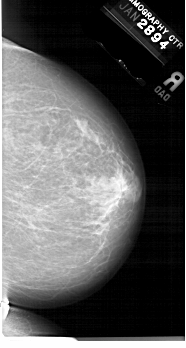

A_1679_1.RIGHT_MLO

RIGHT_MLO LINES 6616 PIXELS_PER_LINE 3511 BITS_PER_PIXEL 12 RESOLUTION 43.5 NON_OVERLAY